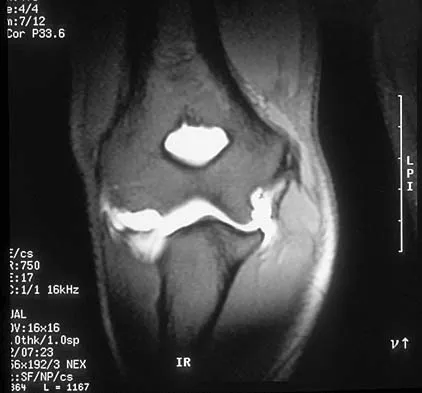

Figure 48 shows an MRI scan of the knee. The arrow is pointing to what structure?

Explanation